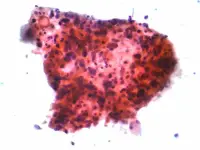

Cancro è una parola ancora temibile. Nell'immaginario collettivo ha quasi sempre una prognosi infausta quando invece i dati statistici ci raccontano sempre più spesso come stiano aumentando le guarigioni e le speranza di vita dopo la diagnosi.

Il cancro è sempre più curabile grazie alle diagnosi precoci e alle scoperte mediche in tutti i campi.

Al di là di una corretta prevenzione primaria e secondaria molto c'è da fare ancora nel campo della ricerca. Perché non tutto il processo della cancerogenesi e della formazione di metastasi è noto. Ogni cancro è diverso da un altro perché ogni individuo è diverso. Qui sta la grande difficoltà nel capire l'origine e cercare la cura.